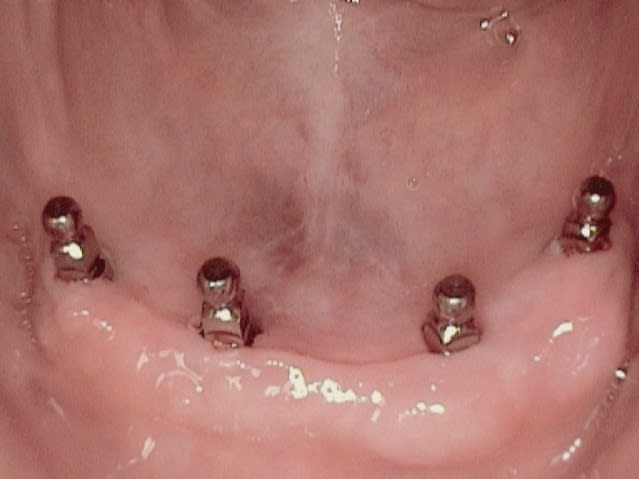

Le cas présenté ci-haut avec 4 implants, c'est triste que les deux implants centrales soient linguals au bourrelet de gencive kératinisé....dans la muqueuse mobile. Problèmes et douleurs à prévoir chez ce patient peu importe la sorte d'implant utilisé...besoin greffe de gencive.

Les implants ressemblent au Q-Implant de Trinon Titanium Gmbh mais avec un collet micro filleté.

ta remarque est très bien, il est vrai qu il semble que ca soit trop lingual les deux implants au centre, mais ils sont placés juste au milieu de l´os ( radio DVT). je suis d accord avec toi ca serait un problème grave si les implants étaient placés dans la muqueuse mouvable buccale de l os, mais dans la muqueuse mouvable linguale il n y a pas de problème pour les patients le but étant de forer au milieu de l os, ceci dit si l os avait éte configuré autrement et que je n aurai donc pas du forer à cette endroit j aurai préféré car il y a meilleur comme configuration ...

pour montrer mieux, j ajoute deux cas . Le premier cas ( première photo)les implants en position 34 et 42 sont fait par un dentiste assistant et les implants 32 et 44 par un chirurgien dans notre clinique (pendant un cours) , après l opération on a fait un DVT ,Où tu peux voir que le chirurgien a trouvé mieux le miieu de l´os et que l os buccal est plus fort...